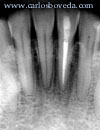

Incisivo

Central Inferior Izquierdo

Primer

Premolar Inferior Derecho